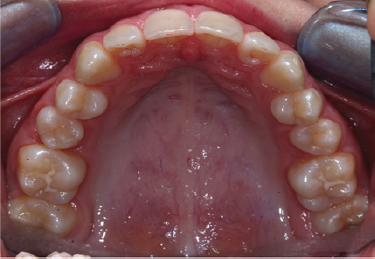

A 15-year-old female came to our visit with medical history of ALGS. The patient was in treatment with ursodeoxycholic acid as she presents perimembranous inter ventricular defect and bilateral articular restenosis. The genetic background of the patient shows a deletion of chromosome 20p en-compassing JAG1. Clinical examination revealed recognizable characteristics ALGS traits: broad forehead, deep-set eyes with eye-socket, maxillary hypoplasia, maxillo-mandibular retrusion (Figure 1 & 2). The patient presented molar class II on both sides, a normo-overjet and a 4mm overbite (Figure 3). An intra-oral examination revealed presence of a talon cusp on the element 22 (Figure 4) infra-occlusion of the elements 75 and 85 (Figure 5). Panoramic radiograph showed a agenesis of the elements 35 and 45. Also 180 degrees rotation of the element 15 was found (Figure 6). Her dental management so far has involved improving of oral hygiene and placing fissure sealant on the molars. Aggressive preventive oral care is a primary need in those patients. Dental development was normal for the patient's chronological age and there was no carious lesion. No previous publication reported AGS patient presenting single or multiple agenesis, since AGS is a rare syndrome more cases are needed to investigate to exclude any possible relationship.

Figure 4: Upperdentalarch figure.